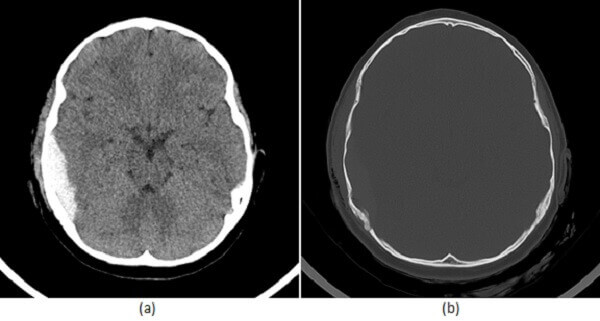

Epidural hematoma is often due to trauma that causes an accumulation of blood between the dura mater and the skull when the middle meningeal artery is injured. On CT scan, the appearance of the hematoma has been described as “lentiform”. Also, there is often a lucid interval after trauma in which the patient regains consciousness temporarily.

Subdural hematoma is common in chronic alcoholics as well as the elderly after a fall. It is often due to laceration of the bridging veins that connect the dura and arachnoid. The CT scan appearance of the hematoma is “crescent-shaped”.